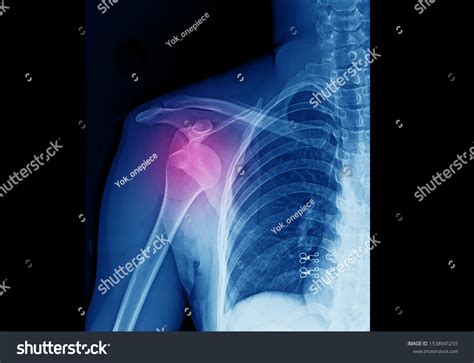

Experiencing a sudden, sharp pain in your shoulder after a fall or a sports-related impact is a distressing ordeal. Often, the first thing medical professionals will order to assess the situation is a Dislocated Shoulder X Ray. Understanding why this imaging is critical, what it reveals, and how it guides your recovery journey is essential for anyone dealing with this common orthopedic injury. A dislocated shoulder occurs when the ball of your upper arm bone (the humerus) pops out of the shoulder socket (the glenoid). Because this area is complex, precise imaging is the gold standard for confirming the diagnosis and ruling out associated complications.

When you arrive at the emergency room or urgent care with a suspected shoulder dislocation, your primary concern is pain relief, but the clinician's priority is diagnostic accuracy. A physical examination can suggest a dislocation, but an X-ray provides the definitive visual proof required to move forward safely.

• Assessing alignment: It helps doctors identify the specific type of dislocation—whether it is anterior (forward), posterior (backward), or inferior (downward).

• Planning for reduction: Knowing the exact position allows the medical team to perform the "reduction" (moving the bone back into place) safely, minimizing further injury to nerves or blood vessels.